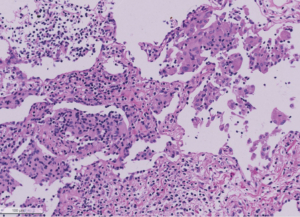

Die Pathogenese der HP ist nicht abschliessend geklärt; man geht davon aus, dass es nach Inhalation der alveolengängigen Antigenen zu einer Infiltration durch mononukleäre Zellen und Neutrophile im Bereich der Bronchiolen, Alveolen und Interstitium mit folglicher Granulombildung kommt [9].

Die bronchoalveoläre Lavage (BAL) zeigt häufig eine relevante Lymphozytose und histopathologisch wird eine bronchiolozentrische Entzündung mit kleinen, histiozytären Granulomen nachgewiesen [7].

Richtungsweisend ist sicherlich die radiologische Bildgebung (HRCT) mit den typischen Befunden der Akutphase wie zentrilobuläre Noduli, Milchglasopazitäten, Airtrapping in Exspiration und in der chronischen Phase zusätzlich Retikulationen und Traktionsbronchiektasen [7].

Da die Diagnosestellung knifflig sein kann, liefern die Autoren Raghu et al. [7] ein Flussdiagramm, welches die Kriterien der passenden Anamnese, HRCT- Bildgebung, Labor, BAL und Histopathologie inkludiert.